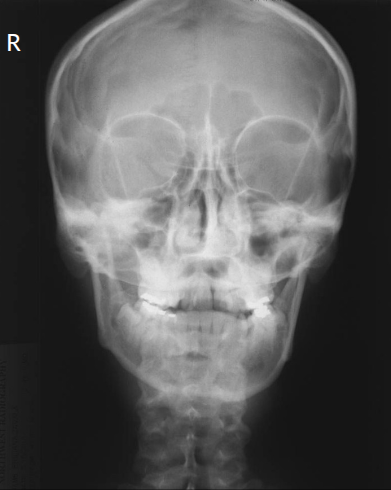

13

Q

what is the correction

A

flex the neck

14

correction (2)

less cephalad angle

or flex neck

nose to the right

15

how is the positioning

correct, issues come from bad CP

16

change the CP

17

(AP) should you correct without a CP change, what would you do

include vertex

5 deg decrease of ceph angle